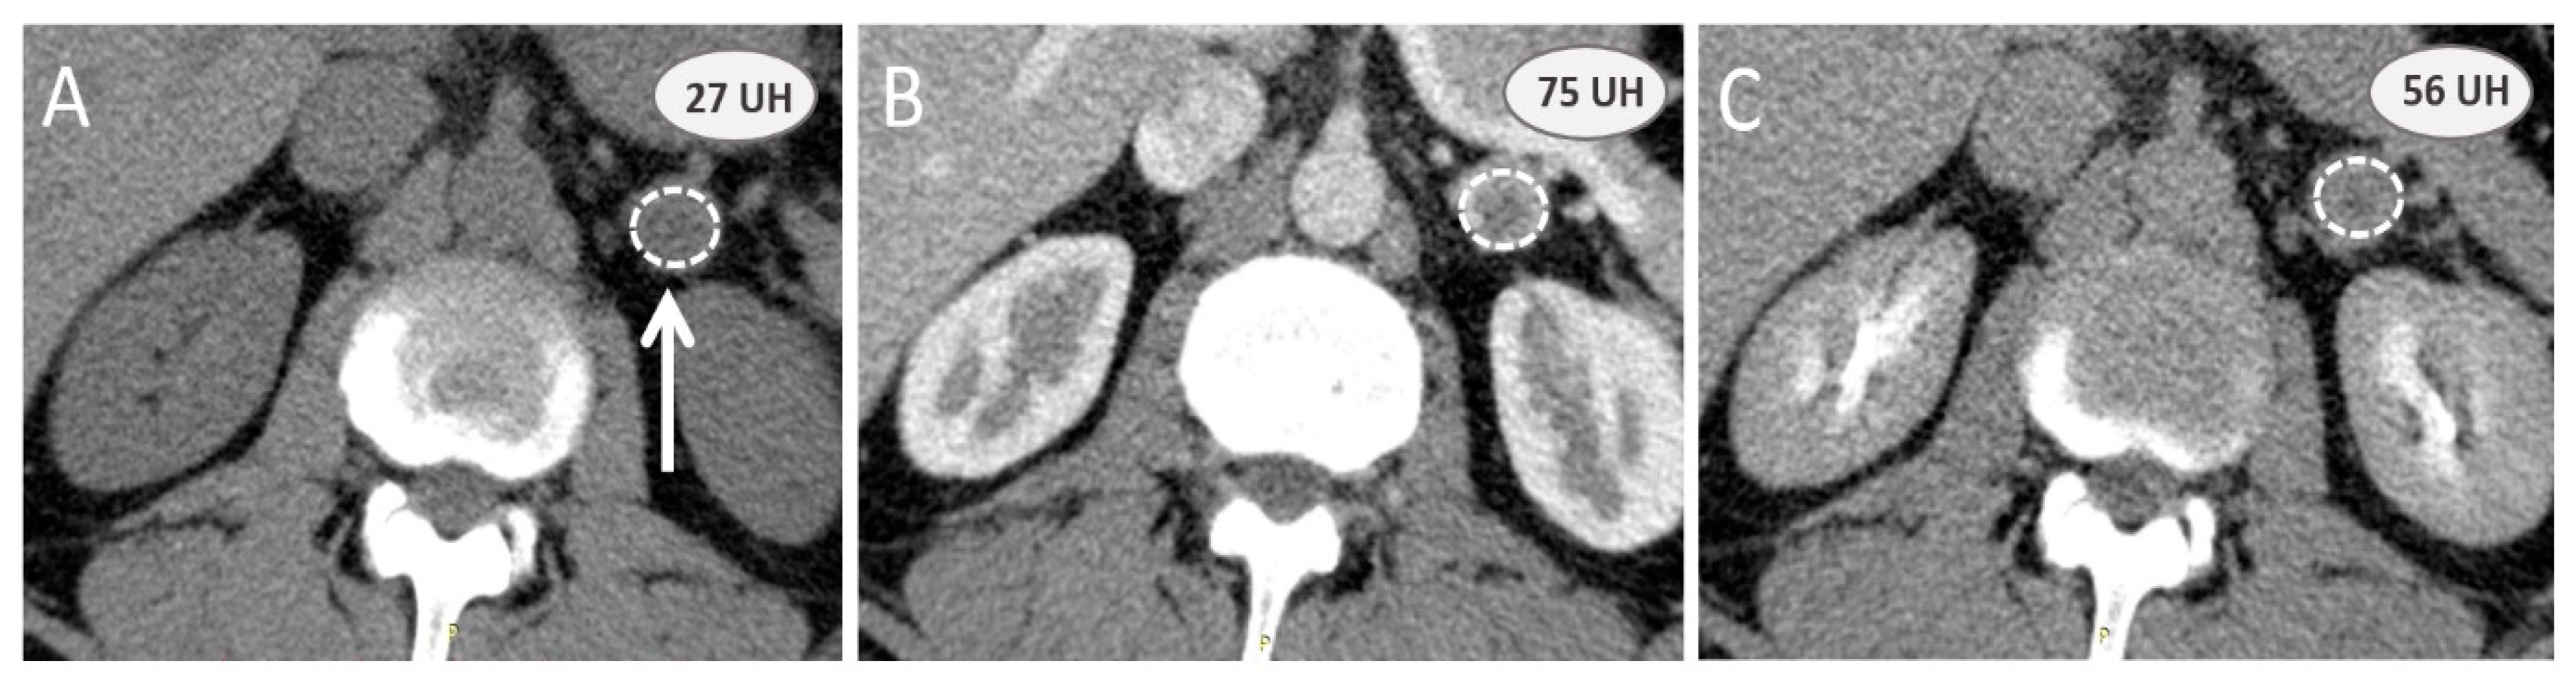

3.2. Additional Value of Contrast-Enhanced Computed Tomography Scan

3.3. Additional Value of Magnetic Resonance Imaging with Chemical Shift Imaging